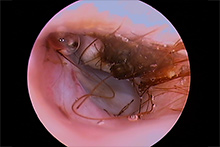

この内視鏡によって、多くの犬猫の耳の中に炎症があることがわかりました。これまでアトピーや皮膚炎、ノミだと思われてきた症状が、実は耳の中に寄生するダニや、外耳炎や中耳炎などによるものであると診断できるようになり、より的確な治療をすることが可能になりました。

耳内視鏡(ビデオオトスコープ)で見た耳の状況

軽度~重度の症状の耳

犬の耳 2 猫の耳 1

猫の耳 1 猫の耳 2